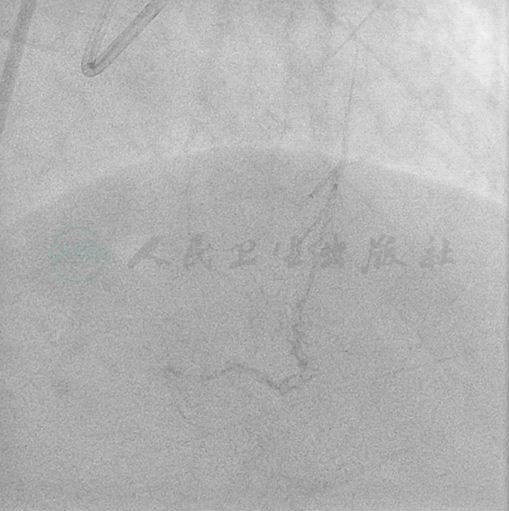

选择右侧桡动脉径路,6F血管鞘。造影发现:右冠自开口处完全闭塞;左冠左主干基本正常;前降支近段轻度狭窄,中远段(第7段)70%~80%狭窄伴狭窄后瘤样扩张,局限;回旋支口部60%狭窄;中间支中段轻度狭窄。回旋支和间隔支见良好侧支循环分别至右冠左室后支及后降支(图1~图3)。

图1 右冠自开口部完全闭塞